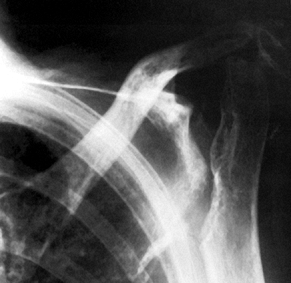

Figure 101.51.

Rheumatoid arthritis of the shoulder. Superior migration of the humeral head, cyst formation, marginal erosion, and severe joint destruction. |